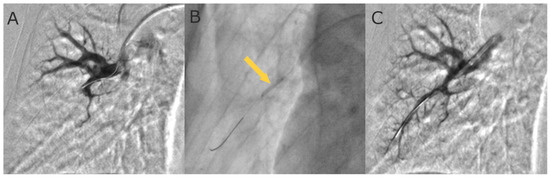

- Kawakami, T.; Ogawa, A.; Miyaji, K.; Mizoguchi, H.; Shimokawahara, H.; Naito, T.; Oka, T.; Yunoki, K.; Munemasa, M.; Matsubara, H. Novel Angiographic Classification of Each Vascular Lesion in Chronic Thromboembolic Pulmonary Hypertension Based on Selective Angiogram and Results of Balloon Pulmonary Angioplasty. Circ. Cardiovasc. Interv. 2016, 9, e003318. [Google Scholar] [CrossRef]

- Stępniewski, J.; Magoń, W.; Waligóra, M.; Jonas, K.; Bochenek, M.; Przybylski, R.; Podolec, P.; Kopeć, G. Hemodynamic effects of balloon pulmonary angioplasty for the treatment of total and subtotal pulmonary artery occlusions in inoperable chronic thromboembolic pulmonary hypertension. Int. J. Cardiol. 2022, 361, 71–76. [Google Scholar] [CrossRef]